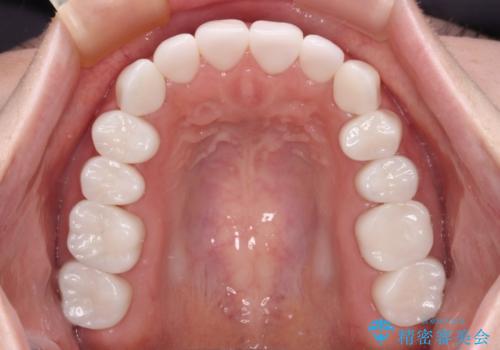

- 奥歯の銀歯をセラミックにしたいとのことで来院された患者様です。

当初は奥歯のみの治療をご希望でしたが、話を進めていくうちに、軽度ではあるものの、幼少期の薬の影響で歯が変色していることがコンプレックスであるということが分かりました。

長年歯の色が塞ぎ込んでいた部分があるとのことで、これを機会に全ての歯を真っ白にするために、オールセラミッククラウンにて補綴治療を行うこととしました。

より白さが目立つように、自然な仕上がりではなく、作り物の雰囲気があるフルジルコニアクラウンにて補綴治療を行いました。